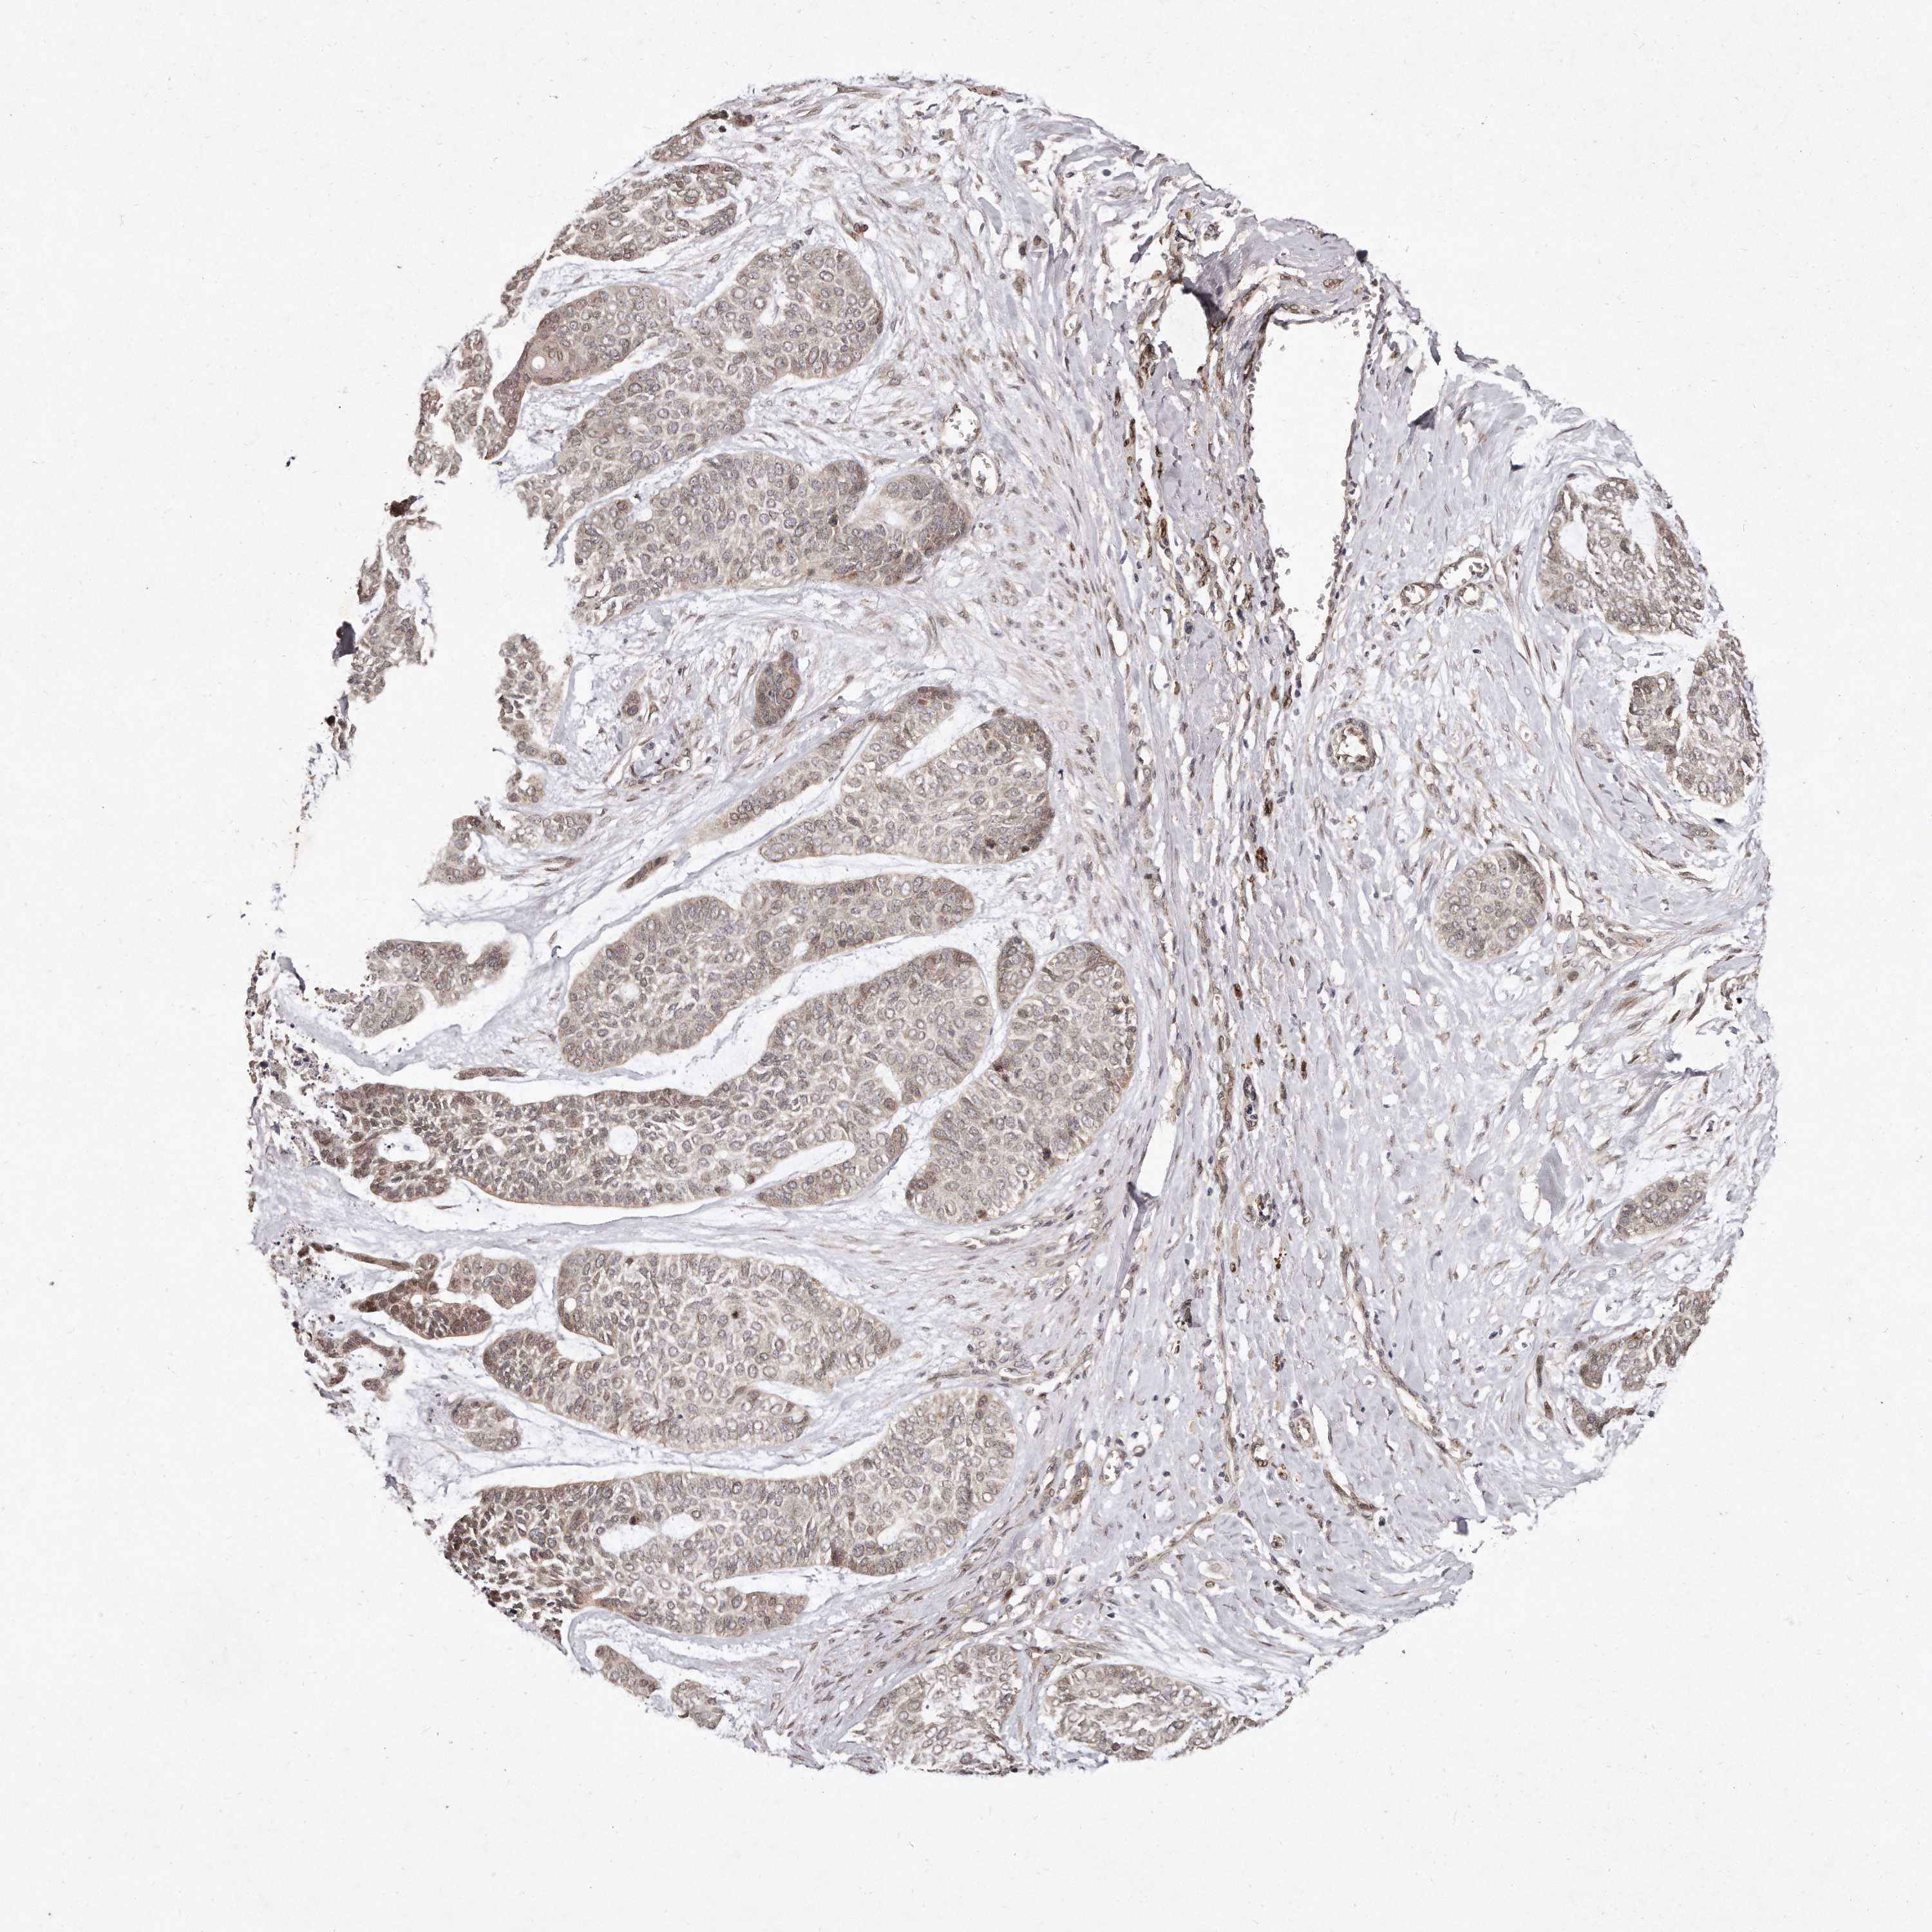

SKIN CANCER - Protein expressioni

A mouse-over function shows sample information and annotation data. Click on an image to view it in a full screen mode. Samples can be filtered based on level of antibody staining by selecting one or several of the following categories: high, medium, low and not detected. The assay and annotation is described here.

Antibody stainingi

Antibody staining in the annotated cell types in the current human tissue is reported as not detected, low, medium, or high, based on conventional immunohistochemistry profiling in selected tissues. This score is based on the combination of the staining intensity and fraction of stained cells.

Each image is clickable and will lead to virtual microscopy that enables deeper exploration of all samples and also displays staining intensity scores, fraction scores and subcellular localization as well as patient and tissue information for each sample.

Antibody HPA027422

Squamous cell carcinoma, metastatic, NOS